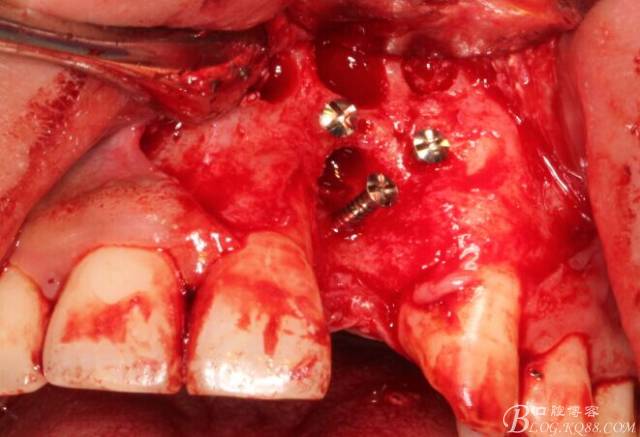

旋入一長(zhǎng)兩短3顆鈦釘。

將自體骨與BIO-OOS骨粉混合植到術(shù)區(qū),蓋生物膜。

縫合。

翻開(kāi)后驚喜的發(fā)現(xiàn),術(shù)區(qū)成骨非常好,去除部分骨才暴露那顆長(zhǎng)鈦釘。

取出影響種植入路的長(zhǎng)鈦釘。